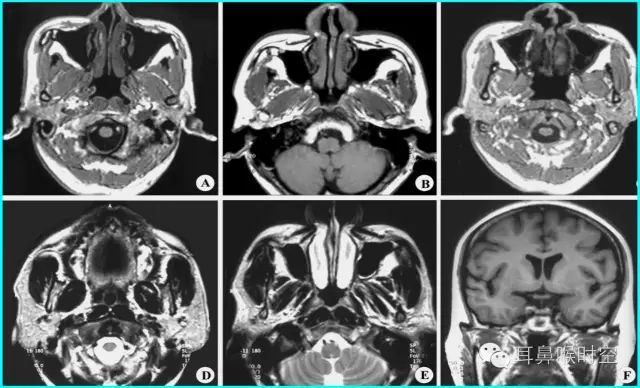

正常组镰刀形(图4)、刀鞘形(图5)为主

镰刀形、刀鞘形,腺样体厚度较薄,下缘凹陷或平直,但均不下凸

肥大组子弹形(图6)、山丘形(图7)为主

肥大组:子弹形、山丘形,腺样体饱滿、下凸,象山丘样突出。在冠状面上腺样体表现为“马鞍形”和“倒置梯形”。

解剖结构:在MRSET1WI 鼻咽部正中矢状面图像上,由于采取薄层断面成像

可以直观显示腺样体本身

清晰显示蝶骨体与枕骨斜坡之间的软骨接合部、鼻后孔间隙、鼻甲、硬腭与软腭上缘的交界面、软腭、会厌软骨等结构

易于测量:非常容易画出A 线及N 线,及测量PAS,了解鼻后孔间隙、鼻甲大小、软腭厚度及后突程度

动态观察:利用MR电影可动态观察鼻咽部随呼吸运动的情况,大大丰富了诊断信息。

任意平面:MR扫描不受体位影响,可行任角度断面扫描与图像重建,从而保证其正中矢状面图像的质量

可重复性:MR是一种无创性检查,无X线辐射危害,不影响儿童生长发育和健康。

MRI表现:

多方位检查

有利于显示肥大的腺样体

呈等T1、长T2信号

增强时可强化